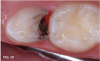

Fig 13. A layer of carious tooth substance debrided painlessly.

Fig 13

Fig 14. SDF applied.

Fig 14

Case 4. At his first dentistry appointment, a 5-year-old with dentinogenesis imperfecta had large caries lesions on the distal of both mandibular primary first molars (Figure 12), along with smaller caries lesions on the distal of the maxillary right primary canine tooth and distal surface of the maxillary right first molar. The distal marginal ridge of the mandibular left second primary molar was fractured and subsequently trimmed smooth, but there was no caries detected in the exposed dentin. Stainless steel crown restoration of the primary first molars would have been difficult to accomplish because of the anatomical form of those teeth, the amount of wear/erosion of the maxillary first molars, and severity of carious destruction of the mandibular first molars. It was predicted that those teeth would be lost to extractions prior to their normal exfoliation time, therefore the goal was to preserve the teeth in place until eruption of the permanent molars to facilitate eventual space maintenance planning. It was thought that SDF could provide an immediate interim solution for caries control for this child, and after this was explained, the boy's father agreed to that treatment immediately at that visit. With cotton roll isolation, top layers of carious tooth substance were debrided from the mandibular first molars using a slow-speed round bur (Figure 13). No anesthetic injections were needed, and the patient related no discomfort. SDF was then painted on the caries lesions of the four teeth (Figure 14), followed by fluoride varnish application (Figure 15). The patient was seen several weeks later for renewed SDF application and dental prophylaxis (Figure 16 and Figure 17).